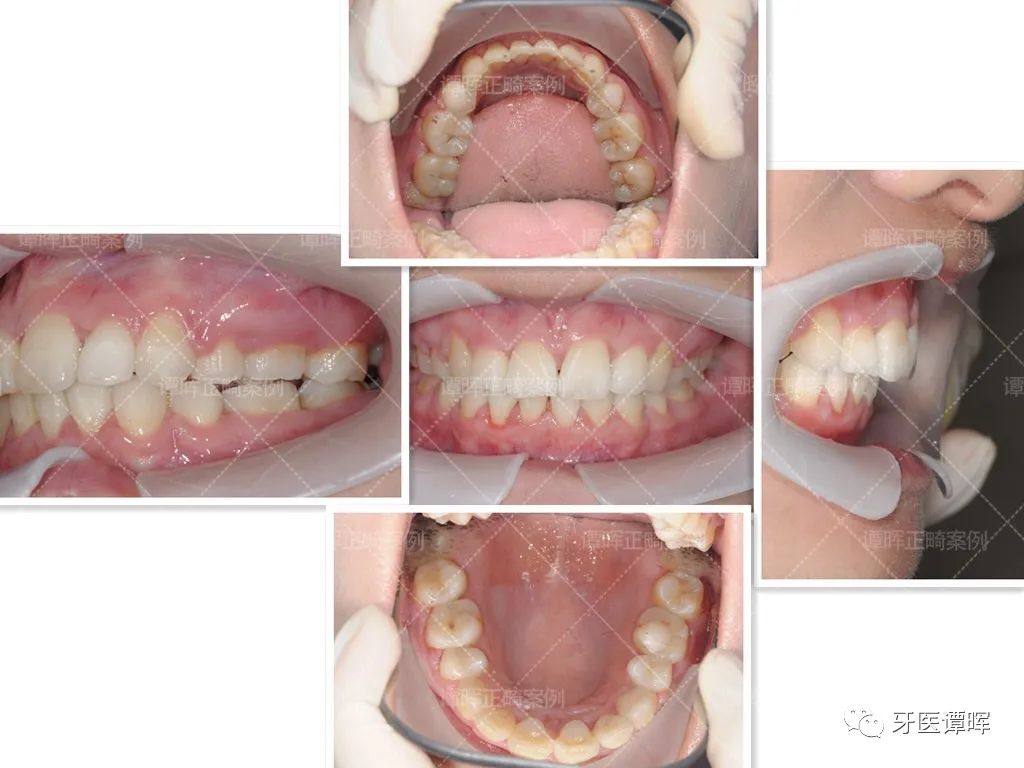

矫正后

全部牙套戴完,终于毕业啦!惊叹牙套神奇的魔力!所有牙齿得到归齐,从美美的笑容图开始看看效果~

从口内照可以看出,牙齿矫正后简直是大逆袭,花了一年半的时间,牙齿即排齐。总之,只要努力就可以改变一切。

从X线分析图可以明显看出前牙往前突内收,上牙的侧切牙也已排齐,牙列排齐。